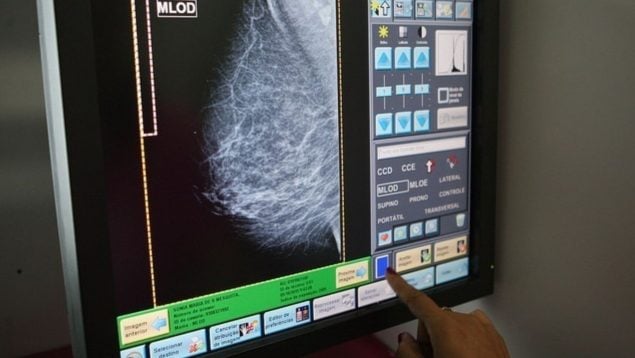

La inteligencia artificial (IA) está transformando la detección precoz del cáncer de mama y puede marcar un nuevo estándar en los programas de cribado poblacional. Las herramientas basadas en IA permiten identificar lesiones sospechosas con mayor precisión, reducir los falsos positivos y agilizar el trabajo de los radiólogos.

«La IA actúa como un segundo lector automatizado, ayudando a priorizar estudios urgentes y a disminuir la carga de lectura», explica Alejandro Tejerina, jefe de Diagnóstico por Imagen del Centro de Patología de la Mama Fundación Tejerina. El especialista ha participado en una sesión científica organizada por la Real Academia Nacional de Medicina de España (RANME) y la Fundación Tejerina, con la colaboración de la Cátedra Extraordinaria de Patología de la Mama en el marco del Día Mundial Contra el Cáncer de Mama.

La Fundación Tejerina ha incorporado dos herramientas de inteligencia artificial —3DQuorum y GAID (Genius AI Detection Hologic)— que ya están transformando la práctica clínica diaria en el diagnóstico del cáncer de mama. Según ha explicado el doctor Tejerina, «3DQuorum genera cortes sintéticos más gruesos a partir de la tomosíntesis completa, permitiendo al radiólogo revisar menos imágenes sin perder sensibilidad diagnóstica. Esto se traduce en menos fatiga visual, menos tiempo de lectura y mayor capacidad para centrarse en los hallazgos clave. Por su parte, GAID (Genius AI Detection Hologic) funciona como un detector complementario que resalta áreas sospechosas que podrían pasar inadvertidas en una primera lectura, aumentando así la seguridad diagnóstica».